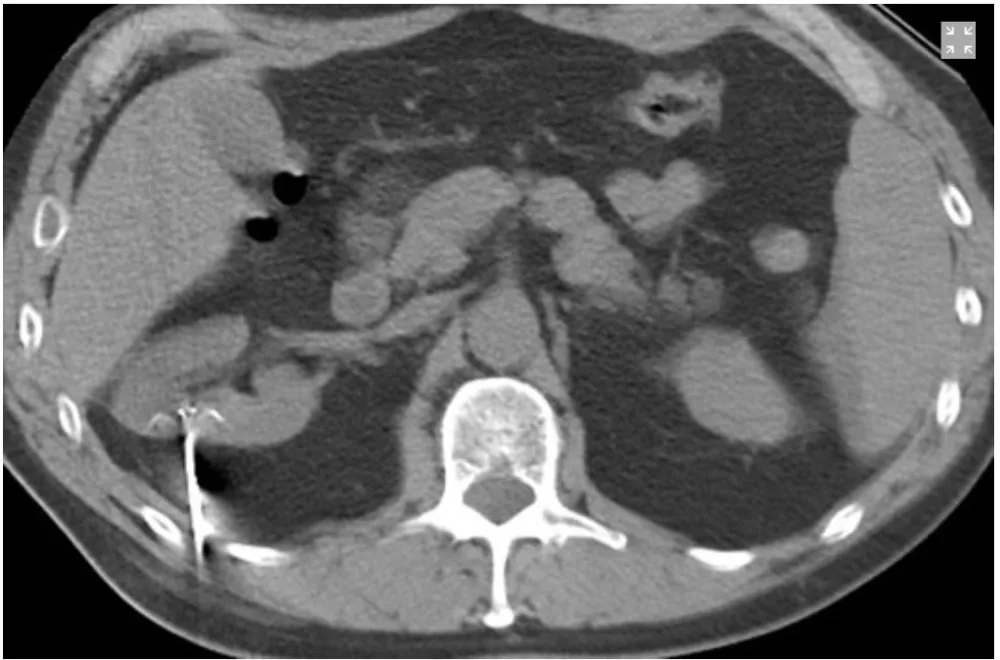

Na imagem 2 é possível identificar a sonda de radioablação.